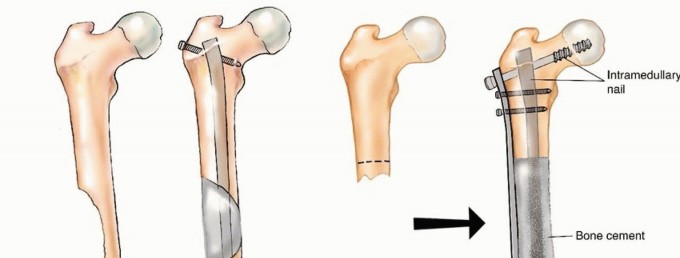

قد يحتاج المرضى المصابون بـ MBD إلى تدخل جراحي لإدارة كسر مرضي وشيك أو موجود بالفعل، أو لتخفيف الألم الشديد المرتبط بآفة متقدمة محليًا لم تستجب للعلاجات الأخرى. هذه "الأزمات الهيكلية" تؤدي إلى فقدان كبير في الوظيفة، وألم، وتدهور في جودة الحياة. في حالات نادرة، قد تُجرى الجراحة لإزالة ورم نقيلي عظمي وحيد بهدف تحسين البقاء على قيد الحياة على المدى الطويل لمرضى مختارين. ومع ذلك، فإن معظم التدخلات الجراحية تكون تلطيفية في المقام الأول، وتهدف إلى التحكم الموضعي في الورم، وتوفير الاستقرار الهيكلي للموقع المعالج جراحيًا، واستعادة الوظيفة الطبيعية بأسرع وقت ممكن.

يُعد الفشل في تحقيق هذه الأهداف أمرًا شائعًا، حيث تصل معدلات الفشل في جراحات MBD إلى 40%، وغالبًا ما تنتج عن تثبيت أولي ضعيف، أو اختيار غير مناسب للزرعات، أو تقدم المرض في مجال الجراحة. إن محاولة علاج كسر مرضي كما لو كان كسرًا ناتجًا عن صدمة ستفشل في معظم الحالات لأن المرض الأساسي يعيق عملية التئام الكسر الطبيعية.

إذا كانت النقيلة قيد الفحص تقع في عظم طويل، فيجب أيضًا إجراء صور أشعة سينية ذات جودة معقولة لكامل امتداد العظم لاستبعاد وجود نقائل إضافية؛ لأن هذه البيانات حاسمة للتخطيط الجراحي. قد تتسبب النقائل التي لم تُكتشف في كسور مرضية عند تحمل الوزن بعد الجراحة وتتطلب جراحة واسعة لإصلاحها.